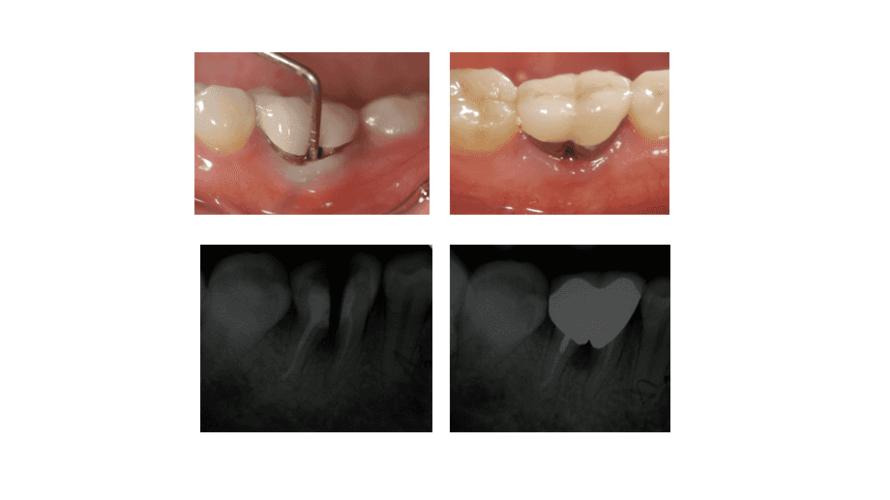

的口腔全景片显示,壮壮右下第一恒磨牙(也叫"六龄齿")牙根分叉已损坏

牙周病学根分叉病变

牙根分叉病变图片

根分叉

牙根吸收